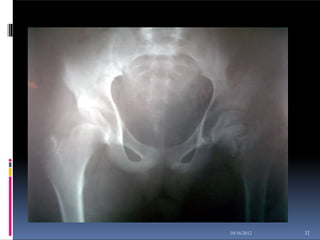

RADIOGRAPHIC EVALUATION

31

 An anteroposterior (AP) view of the

pelvis both

hip in

15

internal rotation and a cross-

table

lateral view of the involved proximal

femur are indicated